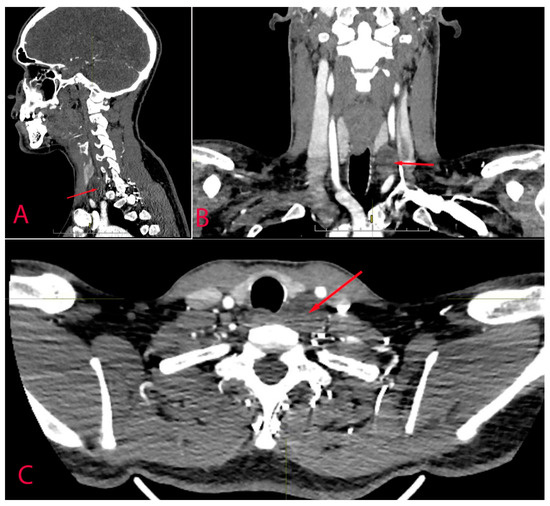

| CT | Schwannoma | Mass that can extend to intervertebral foramen. Contrast enhancement may be helpful as thyroid gland tends to accumulate iodine contrast and may reveal separate plane between gland and tumour. | |